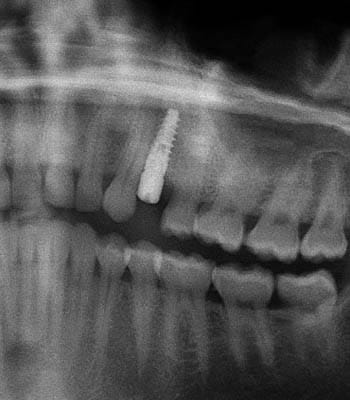

Single Tooth Replacement